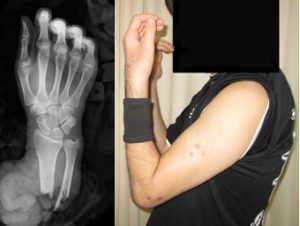

切断指再接着

中環指切断に対して、緊急で再接着手術を行い、切断指を温存することができました。

写真は受傷時のレントゲンと、術後2か月の外観です。

切断前腕再接着

前腕切断に対して、緊急で再接着手術を行いました。

写真は受傷時のレントゲンと、術後2か月後の外観です。